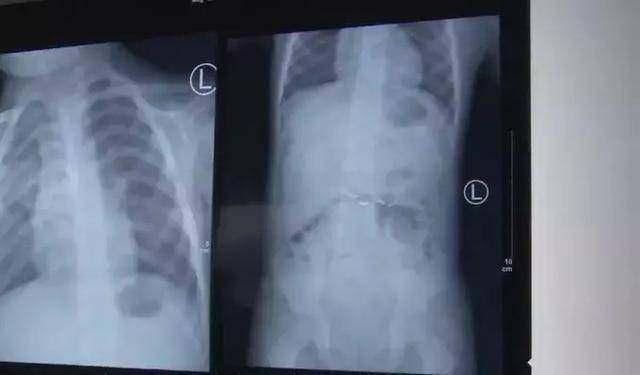

Yang Guihua, phó giám đốc bệnh viện nhi đồng cho biết, sau khi cậu bé được đưa đến bệnh viện, bác sĩ đã quay phim định vị bụng và thấy rằng thủy ngân nằm trong dạ dày.

Phần thủy ngân nằm trong dạ dày của bé.